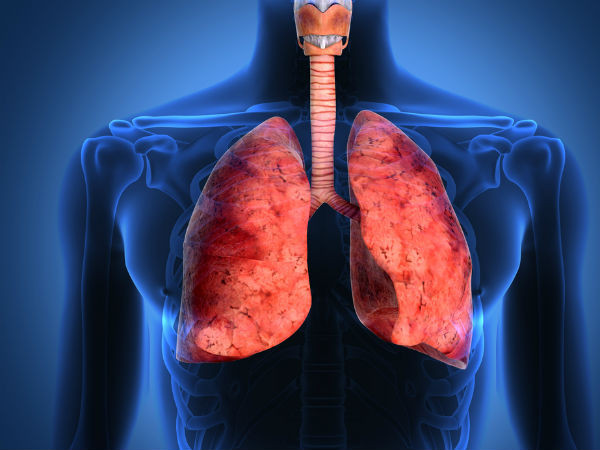

| Đến tháng 12, tình trạng sức khỏe Lý Thiến Sơn không cải thiện mà còn nặng hơn. Cô thường xuyên có cảm giác tức ngực, đau bụng. Mỗi khi ngửi mùi khói thuốc lá do chồng hút, cơn ho của Lý Thiến Sơn càng trầm trọng. (Ảnh minh họa) |